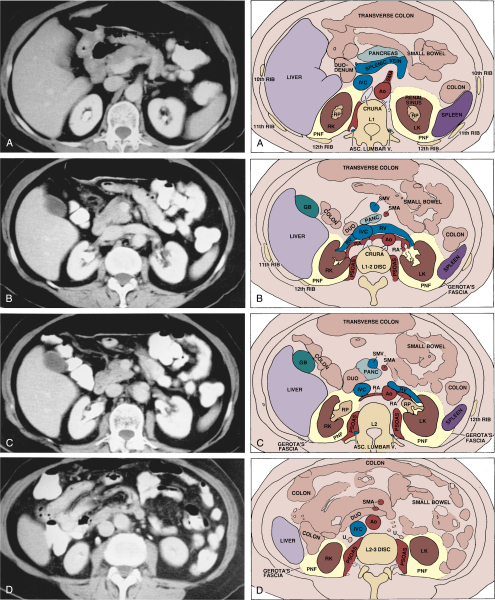

CT anatomy

Sections of the pancreas